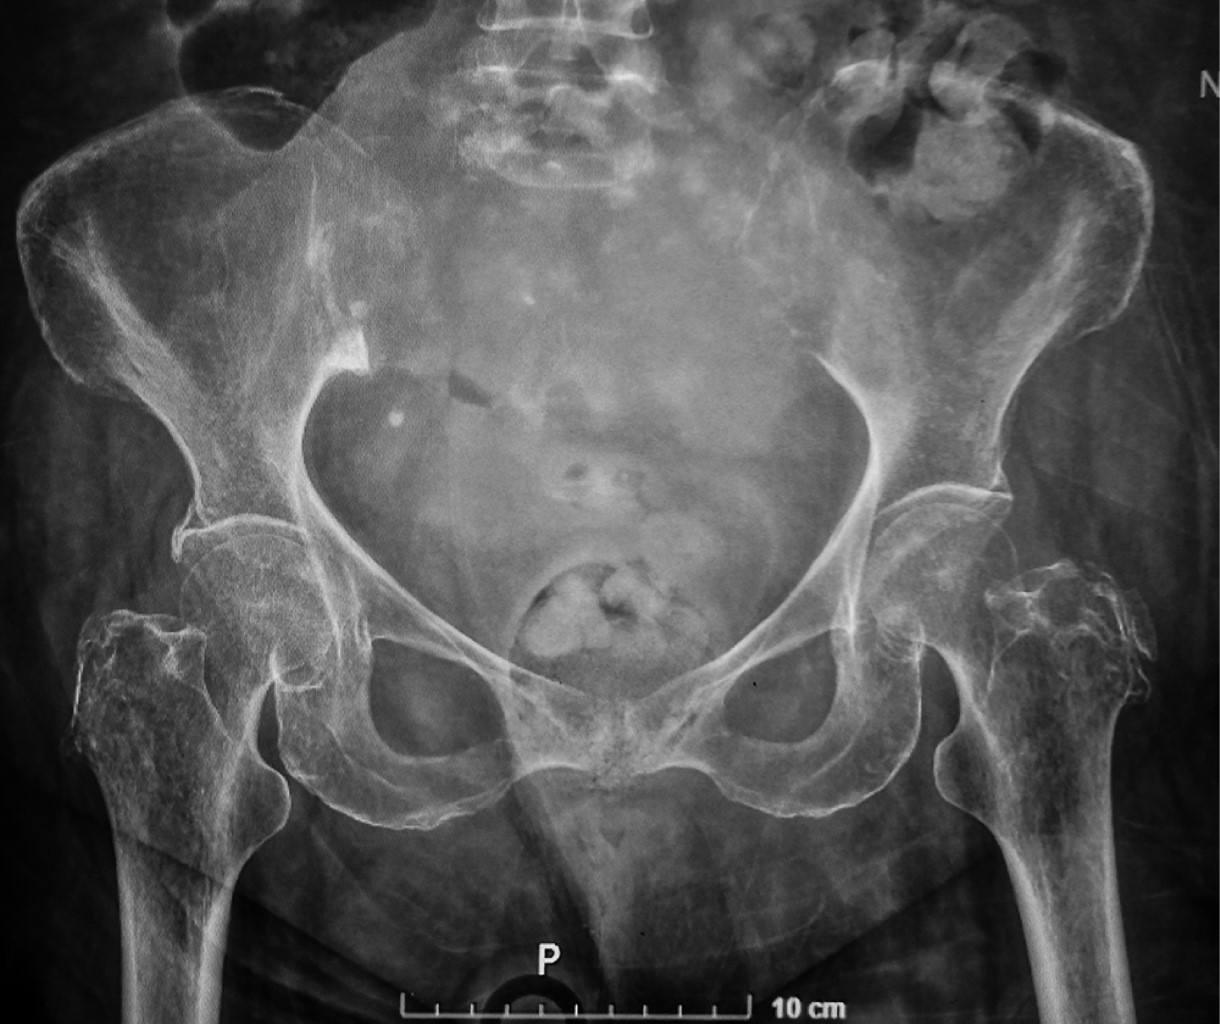

Because of nonspecific symptoms and their insidious development, sacral tumors usually are discovered with advanced imaging studies. Plain radiography is often the first imaging modality performed; however, this often remains inefficient because of the difficulty in evaluating the sacrum on X-ray films2 (Figure 2). When an abnormality is detected in the sacrum on conventional radiographs or clinical suspicion warrants, cross-sectional imaging with computer tomography (CT) and magnetic resonance imaging (MRI) techniques, must be employed.

Figure 2